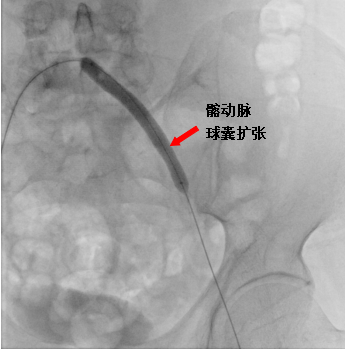

溶栓治疗后,后续又择期引入球囊导管,分别在左侧髂动脉、股浅动脉多处狭窄段进行球囊扩张,扩张后造影见血管扩张良好,血流通畅。